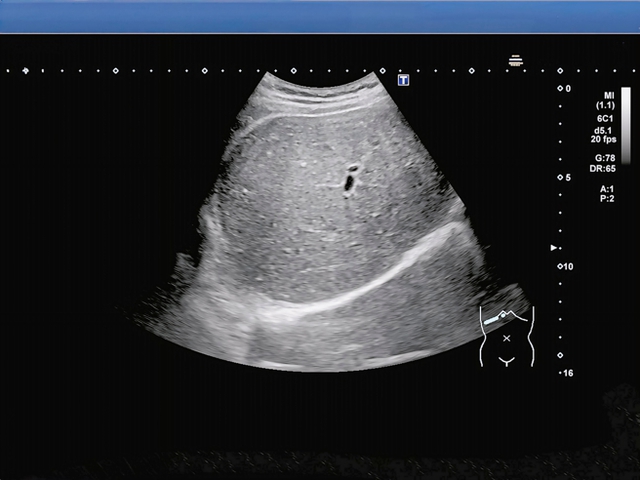

Theo bác sĩ, nam sinh được gia đình đưa đến bệnh viện cấp cứu trong tình trạng đau bụng dữ dội. Kết quả khám cho thấy bệnh nhi bị béo phì, viêm dạ dày cấp tính. Kết quả siêu âm cho thấy gan của nam sinh trắng xóa. Bệnh nhi được chẩn đoán mắc gan nhiễm mỡ nặng.

Gan của nam sinh trắng xóa. (Ảnh: China Times)